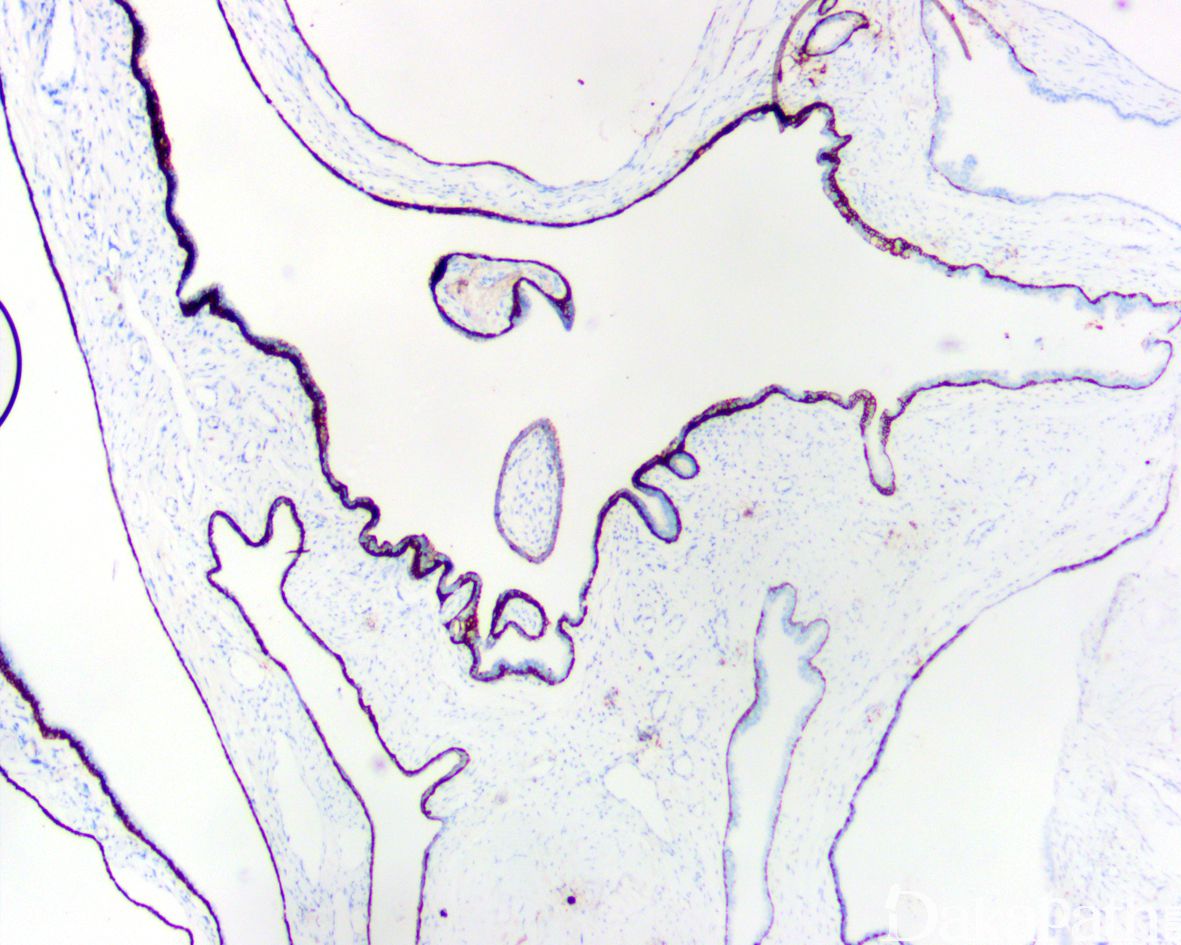

- 囊腔面被覆单层萎缩的偶尔可为增生性的前列腺上皮,可发生高级别上皮内瘤变甚至前列腺腺癌。

免疫组织化学染色:

腺上皮 PAP、PSA 阳性,基底细胞保留,AMACR 阴性。